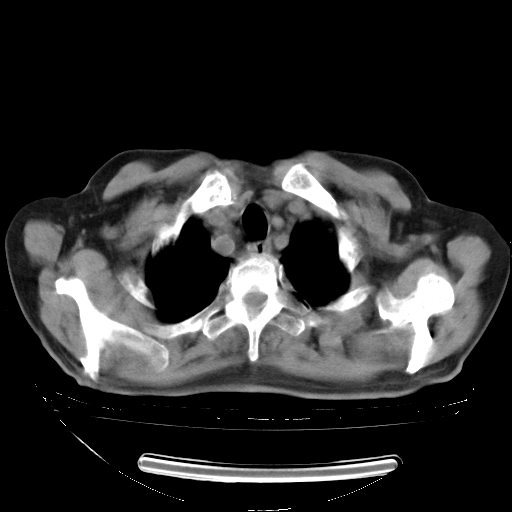

今天复查肺部CT,发现双肺广泛磨玻璃样改变。所以我把3月19日和5月9日相隔50天的肺部CT上传。请大家会诊。

5月9日肺部CT(在4月27日齐鲁医院肺部CT描述部分肺组织磨玻璃样改变,12天后肺组织广泛磨玻璃样改变)

大致读了系列胸部CT:纵隔窗无明显异常,肺窗:从4、27至今:主要是双肺中下野外带可见毛玻璃样改变,目前处于急性肺泡炎阶段,至于原因考虑1、结替组织或胶原血管性疾病所致?2、恶性疾病如恶组在肺部所致的表现或细支气管肺泡癌?3、药物或其它原因如肺蛋白沉着症所致肺泡炎目前不太可能?总之,明天就去请我院的呼吸科、感染科、血液科和临免专家会诊哈。